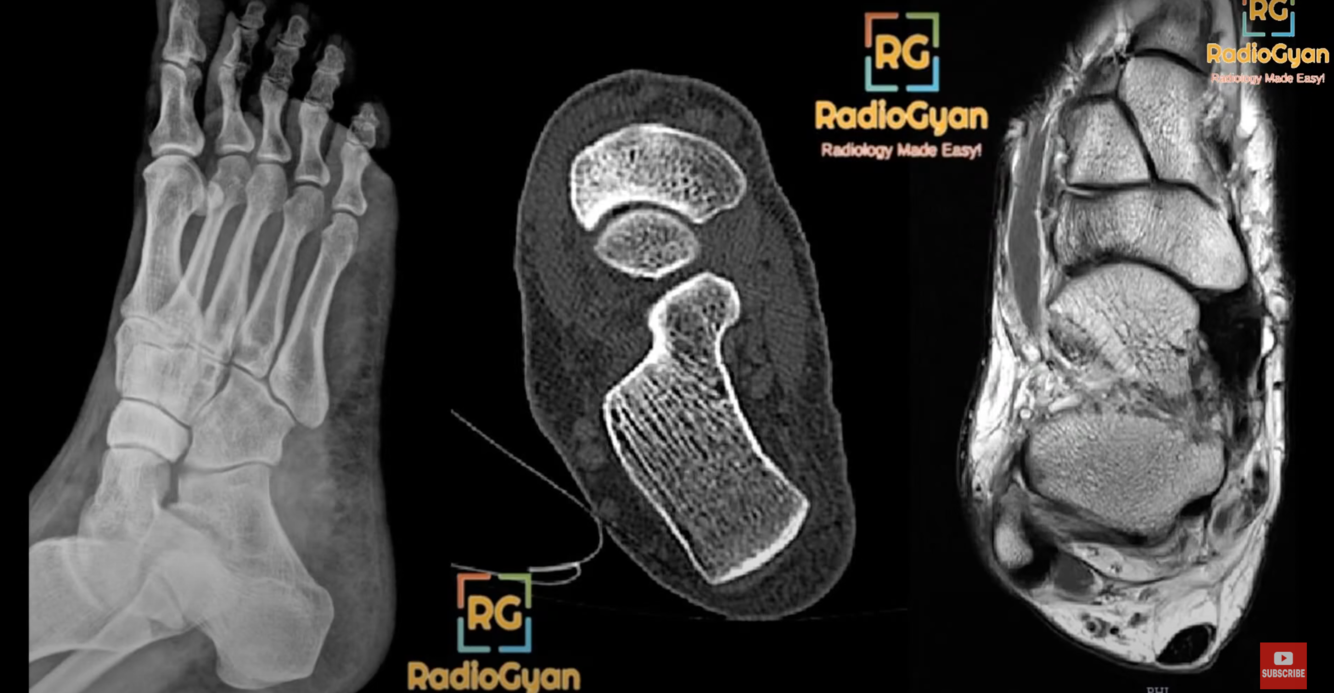

Hands and feet

acro-osteolysis

transverse band of osteolysis in distal phalanges is characteristic

distal to proximal osteolysis is also seen